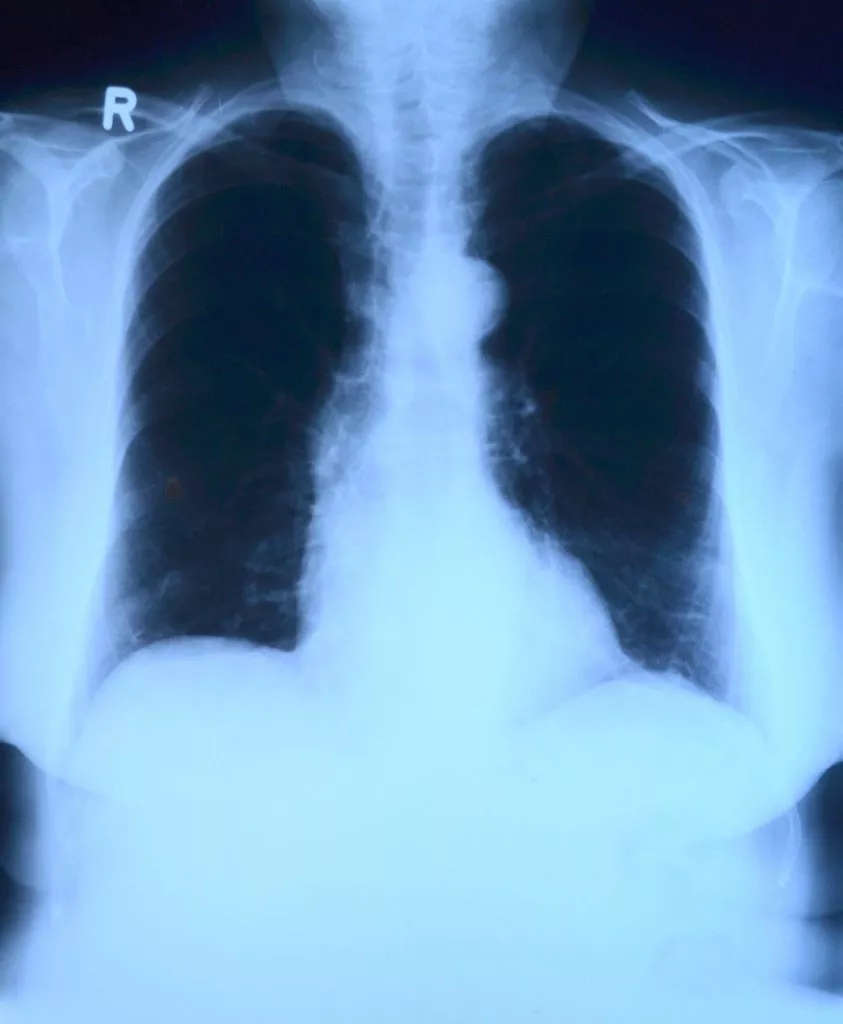

Рентгенологические исследования являются неотъемлемой частью медицинского обследования и широко применяются для диагностики различных заболеваний. Наиболее распространенными и входящими в список обязательных при проведении диспансеризации являются флюорография и рентген легких. Каковы же их принципиальные отличия? Флюорография — это диагностика, при которой через органы и ткани проникают рентгеновские лучи (происходит R-облучение). Как правило, флюорография применяется в качестве скринингового метода, то есть в профилактических целях.

Рентген легких применяется для более тщательного исследования, если заподозрены конкретные заболевания. Этот вид обследования является более информативным, так как позволяет получить более четкий снимок.

• Рентген обладает большим качеством и информативностью изображений, так как рентгеновский снимок по размеру больше, чем флюорограмма.

• По флюорографии врач может оценить легочный рисунок и состояние тканей органа. В результате рентгена доктор получает снимок грудной клетки. При изучении снимка он обращает внимание на структуру мягких тканей и костей.